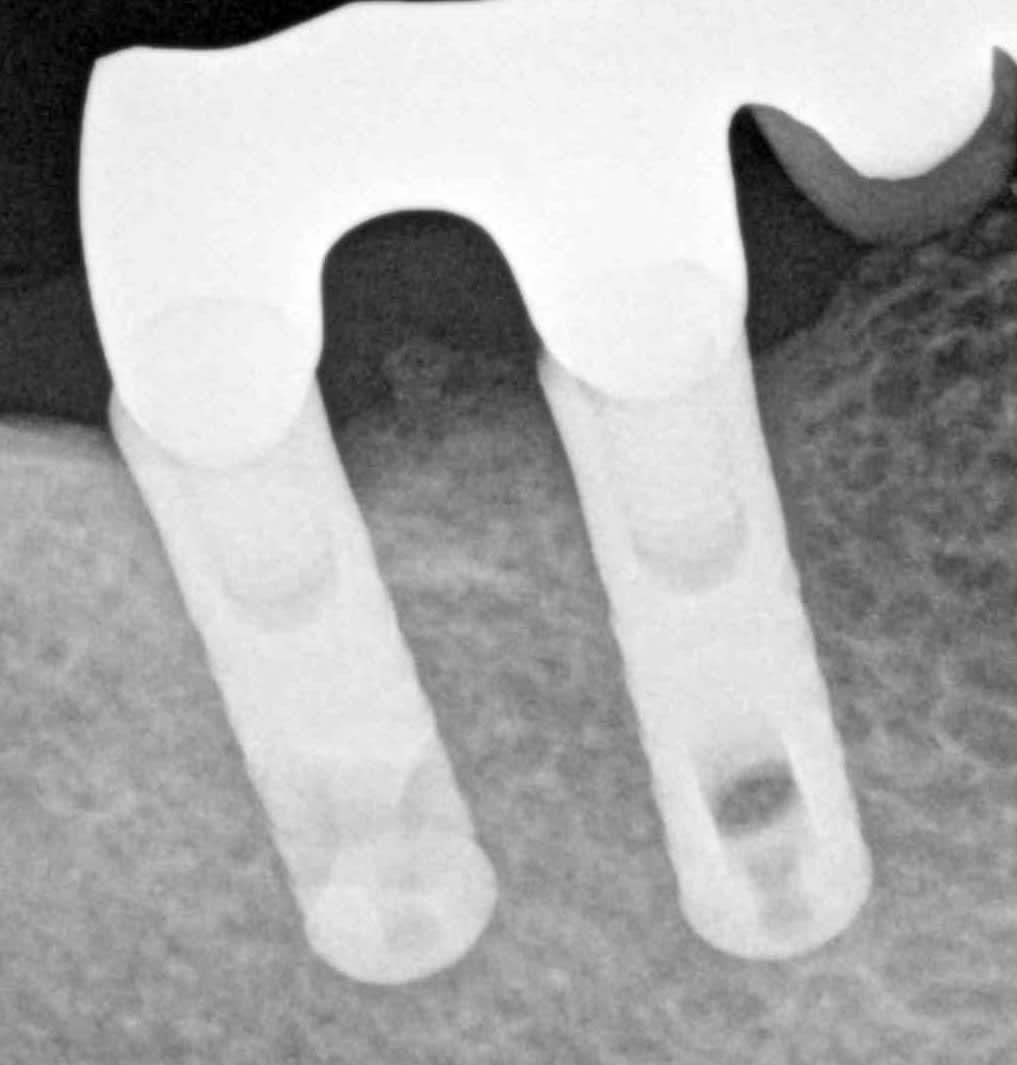

J'ai besoin d'identifier ces deux implants, celui de derrière sera peut-être déposé mais la patiente est âgée et il faut refaire la prothèse dessus qui est défoncée (un beau bridge dento-implanto porté, alors qu'il ne manque pas de dents en dehors des deux implants :D ).

Posés il y a 15 ans environ

rétro correcte quasiment impossible réflexe nauséux ingérable dans cette zone, patiente 83 ans je vais pas la brusquer c'est un zoom de pano.

çà ressemble quad même furieusement à du sterioss....

la radio est trop mauvaise pour être certain de cette identification...

Meilleure rétro que j'ai pu avoir, je sais pas si ça aide beaucoup...

En effet ça ressemble terriblement à un steri-oss flat top ou un THD

je me disais bien que ce design de spire je l'avais déjà vu quelque part...

IMZ twinplus